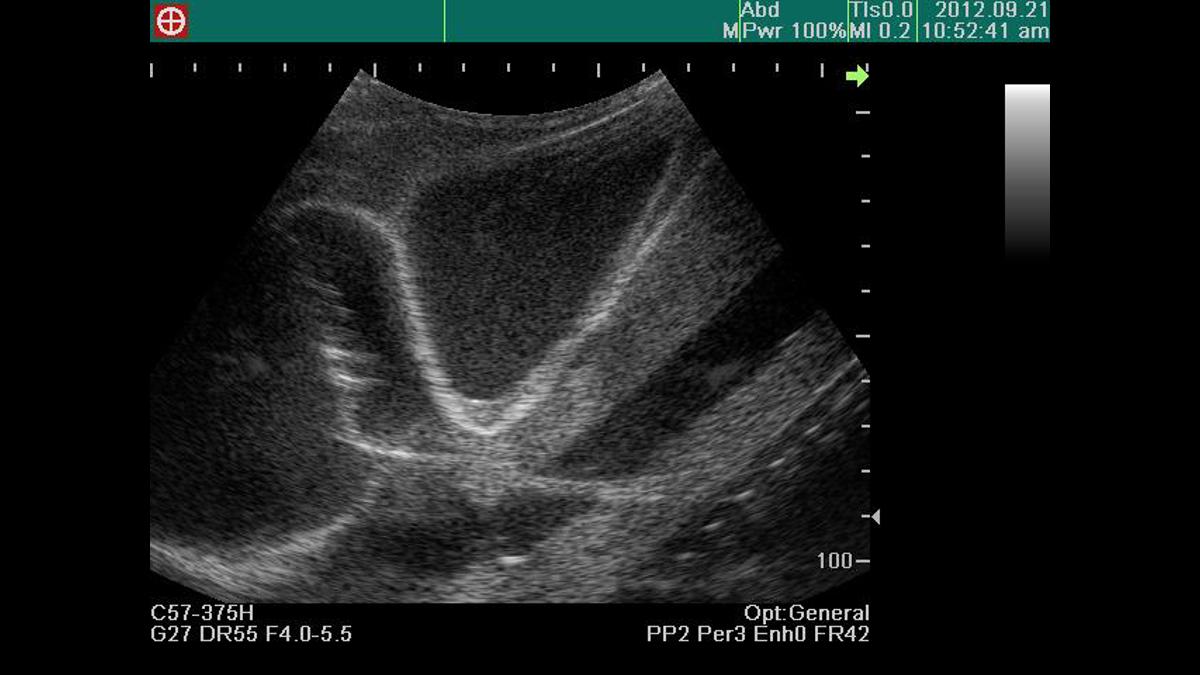

Excellent ultrasound image

Confirmation of ventricles, ribs, pericardium, liver and main artery under ultrasound scanning

Visualization of pericardial fluid using ultrasound scanning

Ability to practice both the subxiphoid approach and parasternal approach